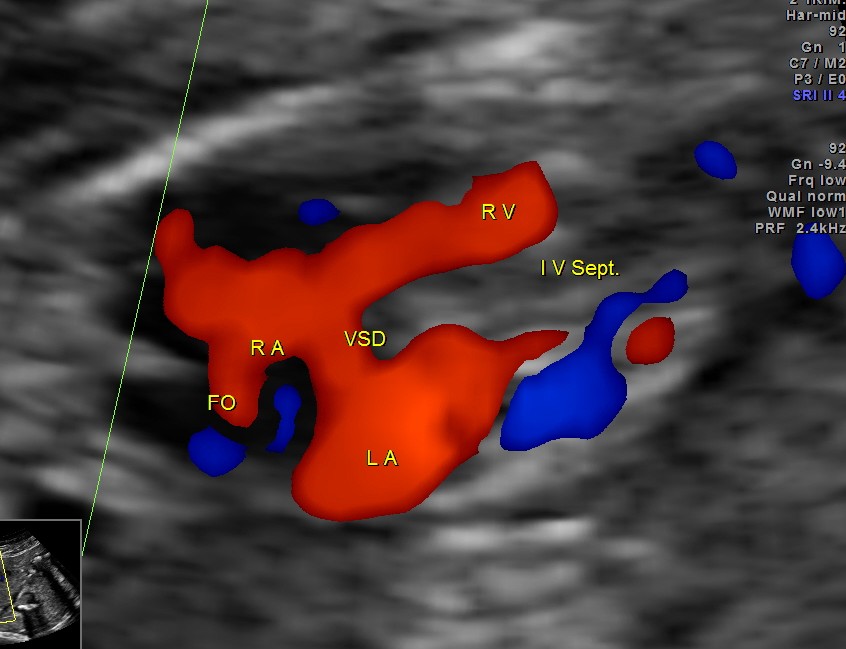

apart from foramen ovale flow , VSD is seen

Ventricular septal defect seen